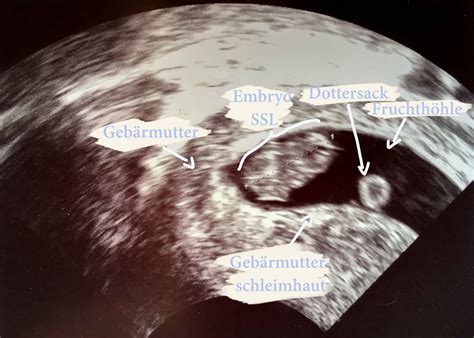

Das sogenannte Windei ist eine Anlage, die sich schon im frühen Stadium der Schwangerschaft nicht weiterentwickelt. Sie wird in der Medizin auch als Abortivei bezeichnet. Es handelt sich um eine Einnistungsstörung (auch Nidationsstörung), die letztlich in einer frühen Fehlgeburt endet. Äußerlich verläuft die Schwangerschaft in den ersten Wochen unauffällig. Die Eizelle wird durch ein Spermium befruchtet und wandert in die Gebärmutter. Dort nistet sie sich in die Gebärmutterschleimhaut ein (Nidation). Die Zellen teilen sich weiter und es bilden sich Plazenta und Fruchthöhle. Auch die Produktion des Schwangerschaftshormons HCG beginnt nun. Daher fällt auch Ihr Schwangerschaftstest positiv aus. Handelt es sich bei Ihrer Schwangerschaft um ein Windei, wächst der Embryo nun entweder nicht weiter oder die Entwicklung stoppt schon nach kurzer Zeit. Im Ultraschallbild ist der wenige Millimeter große Embryo nicht zu erkennen. Es zeigt sich eine leere Fruchthöhle. Zu solch einem Abortivei kommt es bei jeder 20. Einnistung.

Bei der Ultraschalluntersuchung in der Frühschwangerschaft ist nur eine extrem kleine Schwangerschaftsanlage oder eine leere Fruchthöhle zu erkennen. Bei einer zweiten Ultraschall-Untersuchung wird überprüft, ob Gebärmutter und Fruchthöhle nicht weiter wachsen und außerdem der HCG-Spiegel gemessen. Ist kein regelmäßiger Anstieg zu verzeichnen und weiterhin kein Embryo mit einem Herzschlag zu sehen, ist die Diagnose Abortivei bestätigt.

Der Arzt stellt die Diagnose einer Windeizelle durch eine transvaginale Ultraschalluntersuchung fest. Sie wird zwischen der siebten und neunten Schwangerschaftswoche durchgeführt, da der Embryo zu diesem Zeitpunkt in der Regel sichtbar ist.

Es kann auch vorkommen, dass Arzt oder Ärztin beim ersten Ultraschall zunächst von einer normalen Schwangerschaft ausgehen. Denn die Fruchthöhle ist ja intakt. In der 6. SSW könnte es sich also auch um ein sehr kleines Baby handeln. Erst in der 8. SSW können Gynäkologe oder Gynäkologin dann sicher sein, dass es ein Windei ist, da ein lebensfähiges Baby dann zweifelsfrei zu erkennen wäre. Es sei denn, es tritt der sehr seltene Fall ein, dass sich die Fruchthöhle an einer Stelle der Gebärmutter „versteckt“, die vom Ultraschall nur schlecht erfasst werden kann. Ein solcher „Eckenhocker“ offenbart sich dann nach ein bis zwei weiteren Wochen Wartezeit, obwohl zuvor von einem Abortivei ausgegangen wurde.